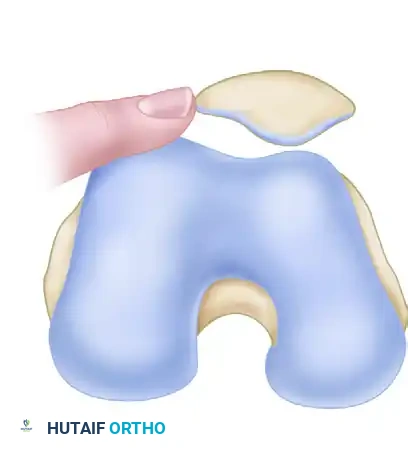

1. Passive Patellar Tilt Test

This test evaluates the tightness of the lateral retinaculum.

- Technique: The patient lies supine with the knee fully extended and the quadriceps relaxed. The examiner attempts to lift the lateral edge of the patella away from the lateral femoral condyle.

- Interpretation: The patella should remain seated in the trochlea. An excessively tight lateral restraint is diagnosed when the patella cannot be lifted past the horizontal plane, demonstrating a neutral or negative angle.